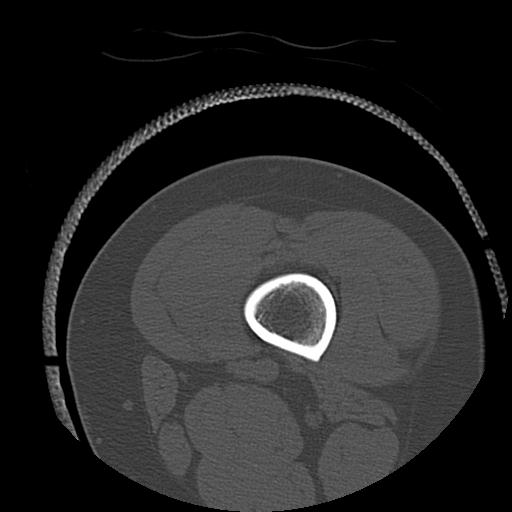

102803 1/12(キウスなし) 1/27 左下腿 4R 30歳女性 左脛骨軸内釘